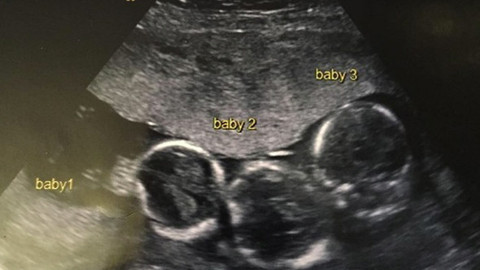

İNGİLTERE'nin Liverpool şehrinde yaşayan Indiana isimli bir kız çocuğu sahibi Becki-Jo Allen ve Liam Tierney çifti, milyonda bir gerçekleşen olayın konusu oldular. oktorlar 23 yaşındaki Becki-Jo Allen’a müjdeli haberi verdiğinde kadın şaşırdı kaldı. Beck-Jo doğum esnasında bir başka sürprizle daha karşılaştı. Meğerse çocuklar tek yumurta üçüzüymüş. Bunun gerçekleşme ihtimali 200 milyonda birmiş. Peki hikaye burada bitti mi sandınız? Hayır hikayenin geri kalanı büyük bir sürpriz. Aile kızlarına kardeş istiyordu ancak üçüzleri olacağını tahmin edemediler. Hamileliğinin ilk haftalarında Becki-Jo hastalandı ve başı ağrımaya başladı. Ultrasona girince üçüzleri olacağını öğrendi. Becki-Jo, Liverpool Echo’ya “Hayatımın en büyük sürpriziydi! Sülalemizde üçüzleri olan kimse yok. Haliyle çok şaşırdık” dedi. Hamileliğinin 31. haftasında Becki-Jo sezaryenle Roman, Rocco ve Rohan’ı dünyaya getirdi. Bebeklerin her biri 1.5 kiloydu ve altı haftalarını yoğun bakımda geçirdiler. Üçüz hamilelik oldukça riskli olarak görülüyor. Hamilelik süreci boyunca ve doğum esnasında komplikasyonlar oluşabiliyor. Üç bebeğin de hayatta kalması nadiren görülen bir olay. Üç bebek de zamanla kilo aldı ve sağlığına kavuştu. Altı haftanın ardından da taburcu edildiler. Doktor, bebeklerin tek yumurta üçüzü olmadığını söyledi. Bebekleri gören herkes ise onların birbirine çok benzediğini söylüyordu. Becki-Jo konuyu daha da araştırmaya başladı. Yapılan testlerin ardından Roman, Rocco ve Rohan’ın gerçekten de tek yumurta üçüzleri olduğu ortaya çıktı. Tek yumurta üçüzlerinin dünyaya gelme olasılığı epey düşük. Üçüz bebeklerin dünyaya gelme olasılığı epey düşük. Mesela ABD’de 2015 yılında sadece dört ailenin tek yumurta üçüzleri oldu. Roman, Rocco ve Rohan birbirlerine inanılmaz benziyorlar. Becki-Jo yine de onları ayırt edebiliyor. Becki Jo, “Sadece uyurlarken onları ayırt edemiyorum. Onun haricinde hepsinin farklı kişiliği var. Bir de hepsinin kaşlarının arasında doğum lekesi var. Roman’ın doğum lekesi daha koyu. Rohan’ın bacağında da leke var” dedi. Üçüzlere haftada 130 bebek bezi gidiyor. Ebeveynlerini ne kadar meşgul ettiklerini tahmin edebilirsiniz. 6 yaşındaki Indiana da kardeşlerini çok seviyor ve onlarla gurur duyuyor. Becki-Jo, “Indiana kardeşlerini çok seviyor. Hiç kıskanmıyor. Onun için biraz üzülüyorum aslında. Üç erkek kardeşle büyümek zor olsa gerek” dedi. İNGİLTERE'nin Liverpool şehrinde yaşayan Indiana isimli bir kız çocuğu sahibi Becki-Jo Allen ve Liam Tierney çifti, milyonda bir gerçekleşen olayın konusu oldular. oktorlar 23 yaşındaki Becki-Jo Allen’a müjdeli haberi verdiğinde kadın şaşırdı kaldı. Beck-Jo doğum esnasında bir başka sürprizle daha karşılaştı. Meğerse çocuklar tek yumurta üçüzüymüş. Bunun gerçekleşme ihtimali 200 milyonda birmiş. İNGİLTERE'nin Liverpool şehrinde yaşayan Indiana isimli bir kız çocuğu sahibi Becki-Jo Allen ve Liam Tierney çifti, milyonda bir gerçekleşen olayın konusu oldular. oktorlar 23 yaşındaki Becki-Jo Allen’a müjdeli haberi verdiğinde kadın şaşırdı kaldı. Beck-Jo doğum esnasında bir başka sürprizle daha karşılaştı. Meğerse çocuklar tek yumurta üçüzüymüş. Bunun gerçekleşme ihtimali 200 milyonda birmiş. İNGİLTERE'nin Liverpool şehrinde yaşayan Indiana isimli bir kız çocuğu sahibi Becki-Jo Allen ve Liam Tierney çifti, milyonda bir gerçekleşen olayın konusu oldular. oktorlar 23 yaşındaki Becki-Jo Allen’a müjdeli haberi verdiğinde kadın şaşırdı kaldı. Beck-Jo doğum esnasında bir başka sürprizle daha karşılaştı. Meğerse çocuklar tek yumurta üçüzüymüş. Bunun gerçekleşme ihtimali 200 milyonda birmiş. İNGİLTERE'nin Liverpool şehrinde yaşayan Indiana isimli bir kız çocuğu sahibi Becki-Jo Allen ve Liam Tierney çifti, milyonda bir gerçekleşen olayın konusu oldular. oktorlar 23 yaşındaki Becki-Jo Allen’a müjdeli haberi verdiğinde kadın şaşırdı kaldı. Beck-Jo doğum esnasında bir başka sürprizle daha karşılaştı. Meğerse çocuklar tek yumurta üçüzüymüş. Bunun gerçekleşme ihtimali 200 milyonda birmiş. İNGİLTERE'nin Liverpool şehrinde yaşayan Indiana isimli bir kız çocuğu sahibi Becki-Jo Allen ve Liam Tierney çifti, milyonda bir gerçekleşen olayın konusu oldular. oktorlar 23 yaşındaki Becki-Jo Allen’a müjdeli haberi verdiğinde kadın şaşırdı kaldı. Beck-Jo doğum esnasında bir başka sürprizle daha karşılaştı. Meğerse çocuklar tek yumurta üçüzüymüş. Bunun gerçekleşme ihtimali 200 milyonda birmiş. İNGİLTERE'nin Liverpool şehrinde yaşayan Indiana isimli bir kız çocuğu sahibi Becki-Jo Allen ve Liam Tierney çifti, milyonda bir gerçekleşen olayın konusu oldular. oktorlar 23 yaşındaki Becki-Jo Allen’a müjdeli haberi verdiğinde kadın şaşırdı kaldı. Beck-Jo doğum esnasında bir başka sürprizle daha karşılaştı. Meğerse çocuklar tek yumurta üçüzüymüş. Bunun gerçekleşme ihtimali 200 milyonda birmiş. İNGİLTERE'nin Liverpool şehrinde yaşayan Indiana isimli bir kız çocuğu sahibi Becki-Jo Allen ve Liam Tierney çifti, milyonda bir gerçekleşen olayın konusu oldular. oktorlar 23 yaşındaki Becki-Jo Allen’a müjdeli haberi verdiğinde kadın şaşırdı kaldı. Beck-Jo doğum esnasında bir başka sürprizle daha karşılaştı. Meğerse çocuklar tek yumurta üçüzüymüş. Bunun gerçekleşme ihtimali 200 milyonda birmiş.